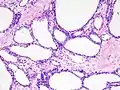

| Micrograph showing a pancreatic serous cystadenoma. H&E stain. | |